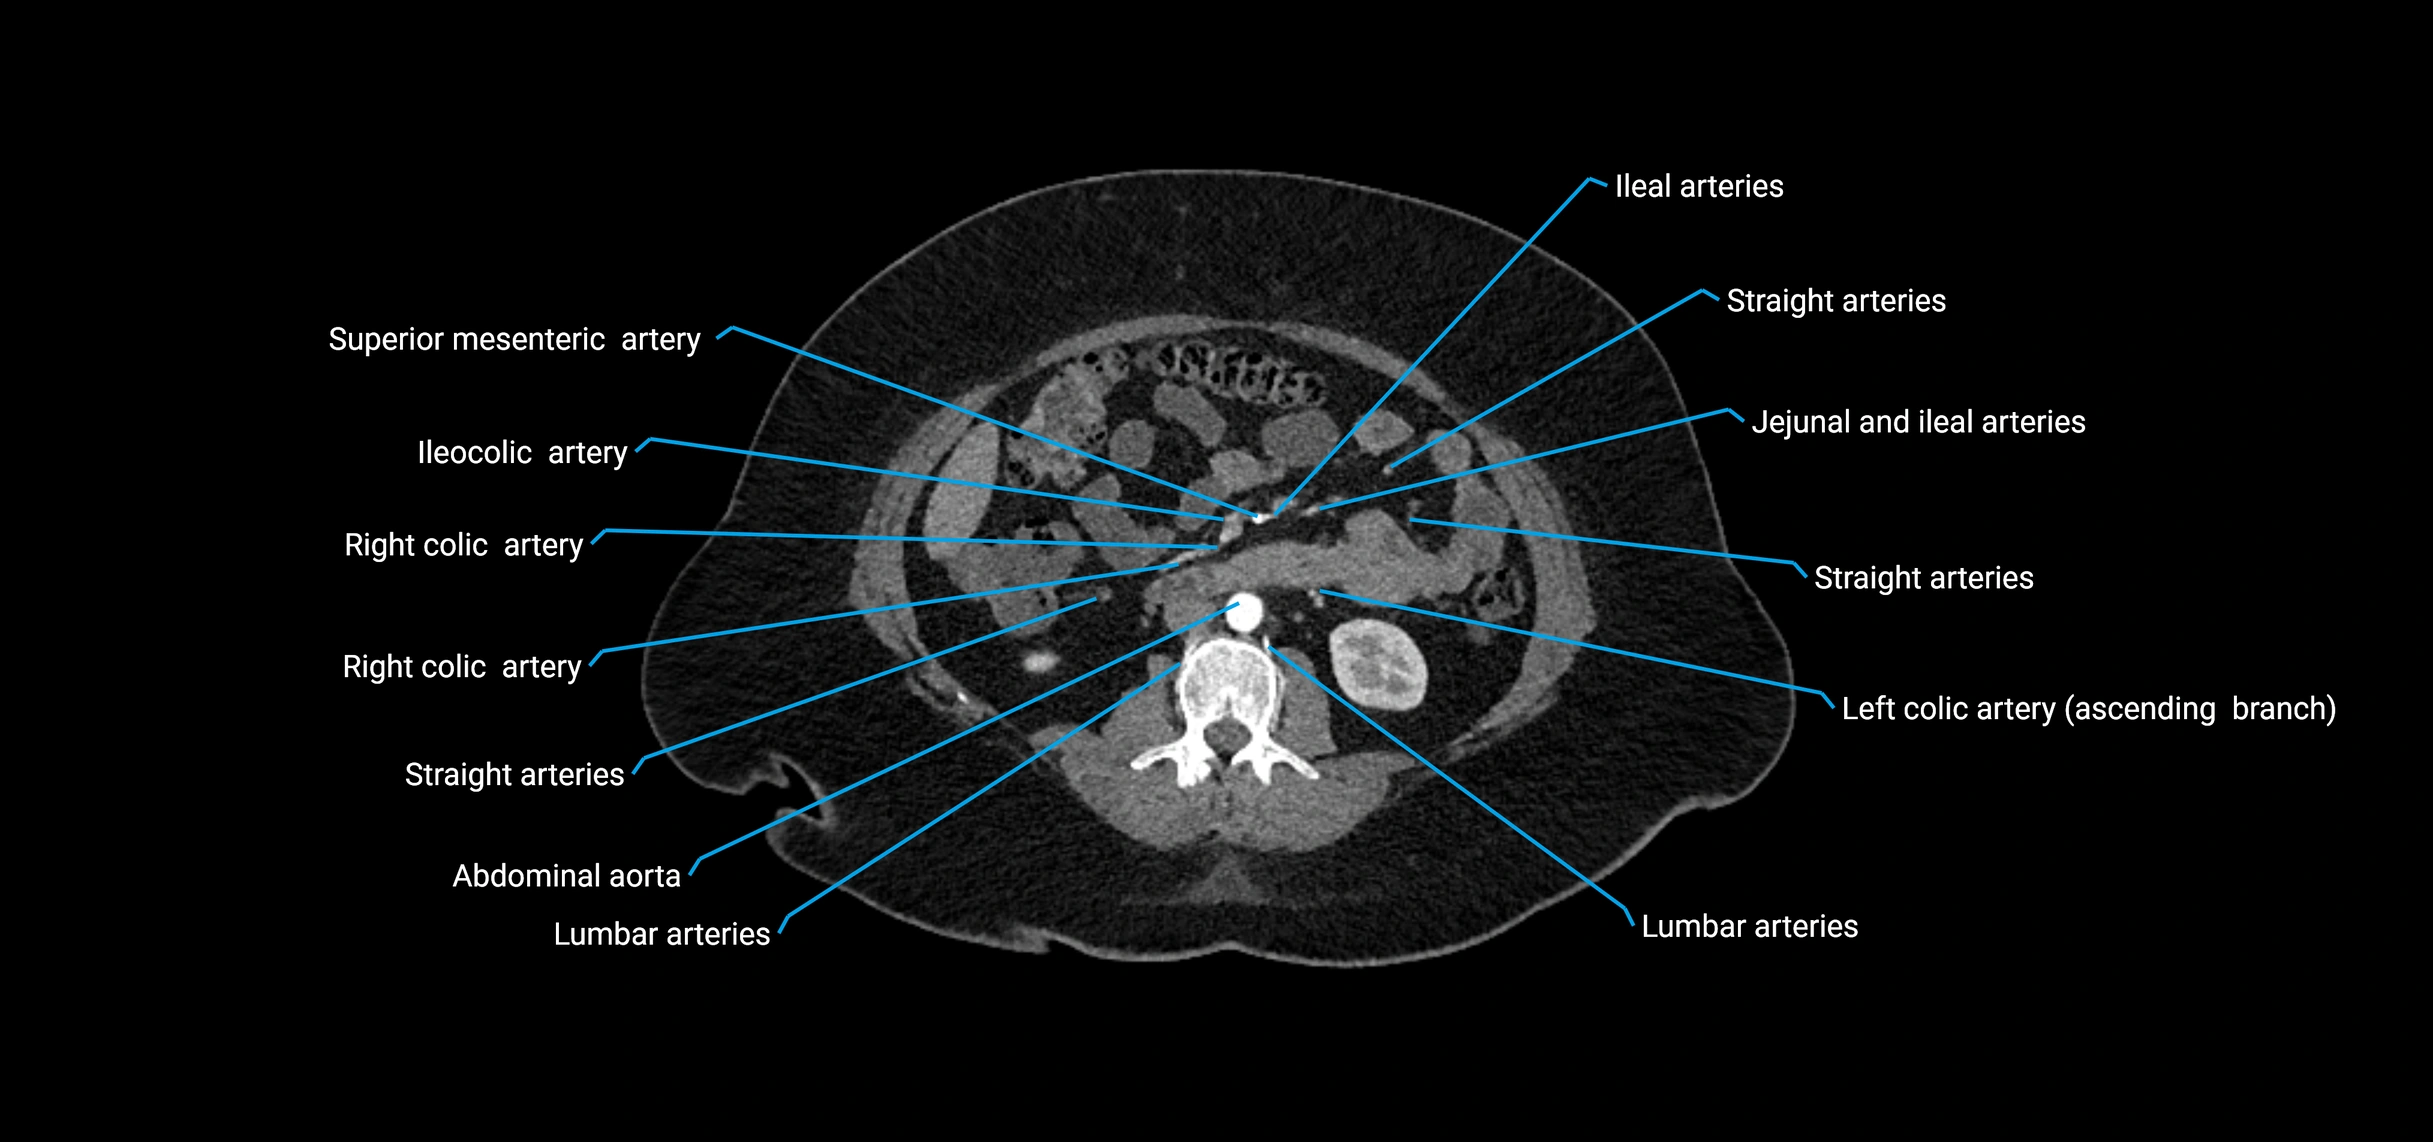

Contrast-enhanced CT (CTA):

• Gold standard for abdominal aortic imaging

• Provides excellent detail of lumen, wall, aneurysm, thrombus, and branch vessels

• Multiplanar and 3D reconstructions help in aneurysm measurement, stent graft planning, and dissection evaluation

• Detects acute rupture, traumatic injury, or occlusion with high sensitivity